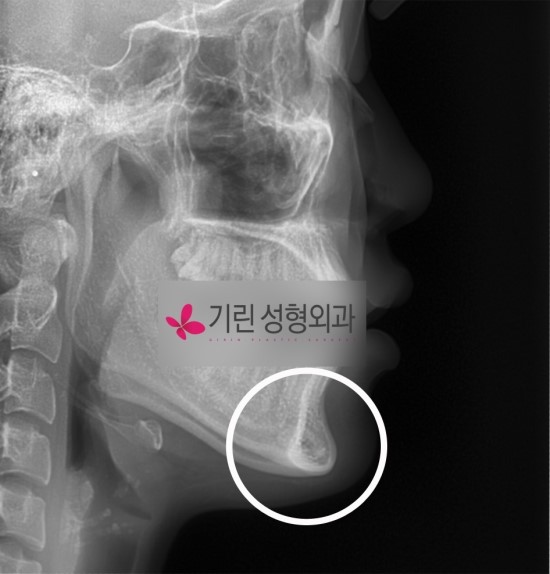

윤곽수술의 하나인 앞턱수술전후 엑스레이로 수술효과정도를 말씀드리겠습니다. 아래사례는 앞턱이 길고 앞으로 발달하여 하관이 길어보이는 사례로 이전포스팅과 동일한 분의 엑스레이입니다.

[안면윤곽수술 전]

수술계획: 하악각이 많이 발달한 편은 아니지만 앞턱이 길고 발달했습니다. 브이라인효과의 극대화와 비율조화를 위해 사각턱수술(귀 밑각부터 앞턱절골선까지)과 앞턱수술(샌드위치 절골)로 길이를 줄였습니다.